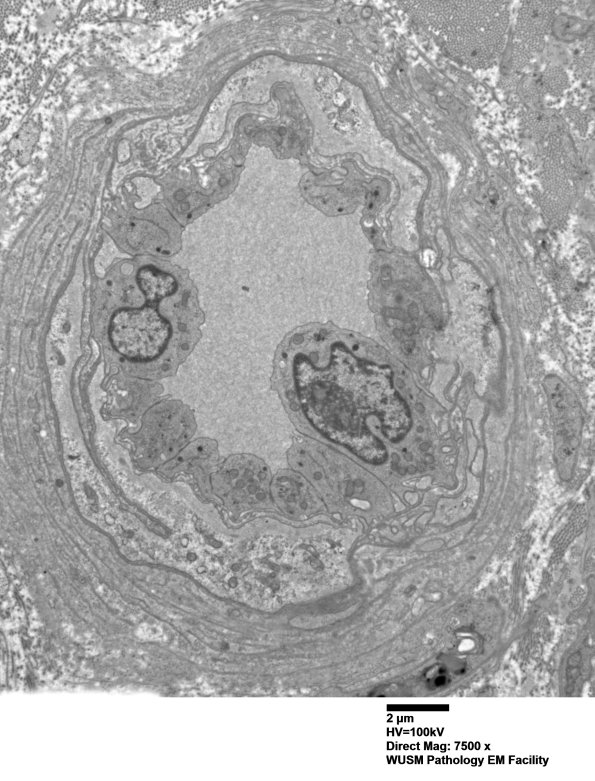

Washington University Experience | VASCULAR | Hypoxia-Ischemia, fetal-neonatal | White Matter | 15B3 (Case 15) HIEM EM 006 - Copy

15B3 (Case 15) HIEM EM 006 - Copy